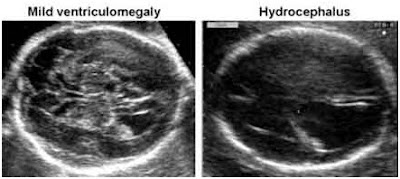

Le diagnostic de ventriculomégalie ne peut que très rarement être porté au premier trimestre ; il s'agit le plus souvent d'un diagnostic du deuxième, voire du troisième trimestre. (10)

Les ventriculomégalies modérées sont une caractéristique échographique pouvant être physiologique, mais aussi être le point d'appel d'une anomalie sévère. Cependant, cette définition est un peu arbitraire puisque le devenir postnatal est probablement lié plus à la présence ou à l'absence d'anomalie de structure du cerveau qu'à la taille de la ventriculomégalie (sauf dans les dilatations extrêmement volumineuses). (10)

Les ventriculomégalies recouvrent un large spectre d'anomalies allant de la ventriculomégalie minime isolée avec un devenir neurologique normal jusqu'aux malformations cérébrales complexes et de pronostic sévère [10].

La découverte échographique d'une ventriculomégalie impose à l'échographiste une description détaillée : uni- ou bilatéralité ; taille ; aspect global du ventricule latéral ; dilatation harmonieuse des différentes cornes ou plus particulièrement de l'une d'entre elles (à noter l'aspect péjoratif d'une dilatation importante des cornes frontales par rapport aux cornes occipitales) ; aspect de la paroi (régulière, épaisse, échogène, grignotée) ; contenu de la dilatation (anéchogène ou présence de matériel

échogène, de travées). (10,11)

Le diagnostic prénatal de ventriculomégalie nécessite de rechercher une étiologie et/ou des malformations associées, et ceci repose sur une étude détaillée de la totalité de l'échostructure encéphalique (aspect du parenchyme, des masses thalamiques, des espaces péricérébraux, des structures de la ligne médiane, de la gyration, de la vascularisation).

Le diagnostic de ventriculomégalie a toujours été porté échographiquement. L'évolutivité de ces ventriculomégalies a pu être appréciée dans tous les cas.

L'hydrocéphalie fœtale est diagnostiquée par échographie, dès la 16e semaine de gestation, elle peut être affirmée entre la 20e et la 22e semaine par la démonstration de ventricules cérébraux anormalement dilatée. Certainement avant 24 semaines et plus particulièrement dans les cas de spina bifida associé, la circonférence de la tête peut être de petite taille plutôt que les grands de la gestation. Une analyse transversale de la tête fœtale au niveau du cavum septum pellucidum fera la démonstration de la partie latérale ventricules dilatés, définie par un diamètre de 10 mm ou plus. Le plexus choroïde, qui normalement remplir les ventricules latéraux sont entourés par un fluide. Une distinction est généralement faite entre les doux, ou à la limite, ventriculomégalie (diamètre de la corne postérieure 10-15 mm) et manifeste une ventriculomégalie ou d'hydrocéphalie (diamètre supérieur à 15 mm). (10)